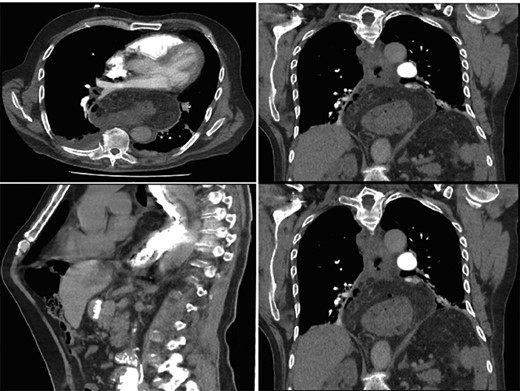

Interval gastroscopy in 2 weeks showed healing mucosal ischemia with slough from 27–30 cm (Fig. 3). Clear fluids were commenced and gradually upgraded to normal diet. Follow-up CT showed no contrast extravasation within posterior mediastinum (Fig. 4) and gastroscopy in 8 weeks showed healed esophagus.

Healing mucosal ischemia from upper, mid and distal esophagus.

CT scan at 2 weeks showing no contrast extravasation in posterior mediastinum.